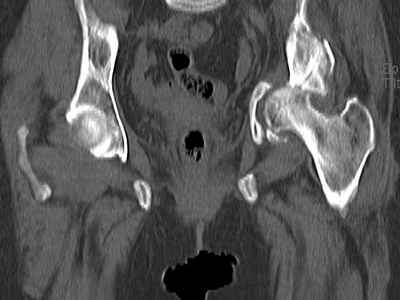

Уважаемые коллеги, возник вопрос по лечению нашей пациентки 60 лет. Около года назад множественная травма: в том числе Т-образный перелом вертлужной впадины.

На сегодняшний день сращение отломков имеется на ограниченных участках, имеется дефект задней колонны вертлужной впадины. Движения неплохие, ходит с костылями, приступая на ногу.

По мнению эдопротезистов при установке антипротрузионного кольца или октопуса не хватит костного материала и необходимо перед протезированием выполнить реконструкцию впадины, иначе чашка протеза неминуемо выпадет.